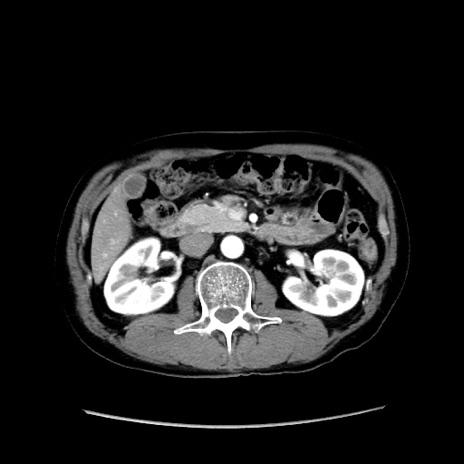

症例37(横断像)

【症例】40歳代 男性

【主訴】腹痛

【現病歴】4時間ほど前に電車に乗車中に臍部上より腹痛出現。徐々に増悪し起立困難となり、救急外来受診。生ものは数日食べていない。今朝お雑煮を食べた。

【身体所見】BT 36.8℃、BP 117/84mmHg、HR 91/min、SpO2 97%、苦悶様、腹部:臍上部広範囲圧痛あり、反跳痛±

【データ】WBC 8100、CRP 0.03